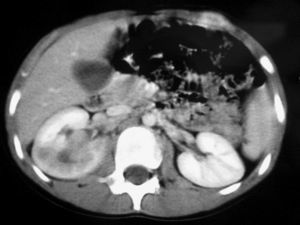

De los 11 nefromas mesoblásticos (con edad y presentación mostrados en la tabla 1) en 7 pacientes el tumor fue sólido y en 4 quístico, con presencia de un polo sólido. En 5 pacientes se encontraron áreas compatibles con necrosis, en dos sangrado intracavitario y en uno función excretora dentro de la masa. Siete pacientes tenían una colección subcapsular y 5 un anillo ecogénico periférico en la ecografía (figs. 1 y 2).

Fig. 1. Nefroma mesoblástico. Niño de 5 meses con masa abdominal palpable. (A) Ecografía abdominal, corte renal izquierdo. Masa en riñón izquierdo predominantemente sólida, con áreas de necrosis (*) y anillo ecogénico en la periferia (flechas). (B) Tomografía computarizada abdominal con contraste intravenoso. Corte al nivel del tercio medio del riñón. Masa en riñón izquierdo que cruza la línea media. Áreas de sangrado (S). Parénquima residual conservado en la periferia posterolateral de la masa (flechas).

Fig. 2. Nefroma mesoblástico. Niña recién nacida con masa abdominal palpable, hipertensión arterial e hipercalcemia. (A) Ecografía abdominal. Corte renal longitudinal. Masa renal izquierda sólida, con colección subcapsular hipoecogénica (flechas negras). Resto de parénquima en polo inferior (flechas blancas). (B) Tomografía computarizada abdominal con contraste intravenoso. Corte al nivel del tercio medio renal. Masa renal hipodensa, con captación de contraste irregular, con anillo hipercaptante en la periferia del tumor (flechas blancas) y colección hipodensa subcapsular (C).

Los estudios de imagen muestran una masa por lo general de gran tamaño, sólida, que suele englobar el seno renal y puede contener, aunque no es frecuente, áreas quísticas, hemorrágicas y necróticas. No presenta buena delimitación con el parénquima sano y puede existir infiltración local de tejidos vecinos1. En uno de nuestros pacientes, estudiado por masa abdominal y cuadro clínico de obstrucción intestinal, se identificó una masa renal que infiltraba el colon, el bazo y la glándula suprarrenal. Un signo ecográfico característico es la imagen en anillos concéntricos hiper e hipoecoicos en la periferia del tumor5,7. En nuestra serie la ecografía demostró una colección hipoecoica subcapsular en 7 pacientes y anillo ecogénico periférico en 5.